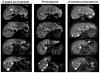

Adoptive cell therapy using tumor-infiltrating lymphocytes (TIL) can mediate objective and durable tumor regressions in patients with metastatic melanoma. CD8+ tumor-reactive TIL are well studied in humans and animals, yet the function of tumor-infiltrating CD4+ T lymphocytes in patient treatments remains controversial. We recently demonstrated that CD4+ TILs are not necessary for objective responses in patients. Coinfusion with tumor-specific CD4 TIL may enhance or increase the durability of tumor regressions, but the number of patients with tumor-reactive CD4 TIL is unknown. We screened 44 CD8+-depleted TIL for in vitro reactivity against autologous tumor. Nine (20%) showed specific reactivity by interferon-γ release assay, of which 8 were specifically blocked by an anti-HLA-DR antibody. Flow-cytometric analysis of these reactive TIL confirmed a high CD4+ composition (median 89%). Highlighting the contribution of CD4+ TIL to tumor regression, a patient with widespread metastatic disease was administered TIL containing HLA class II-restricted tumor activity with high-dose interleukin-2 therapy after lymphodepletion that mediated regression of extensive metastatic disease in the liver and spleen. These results demonstrate that at least 20% of metastatic melanomas contain CD4+ lymphocytes with specific tumor recognition and suggest a possible role for CD4+ cells in the effectiveness of adoptive cell therapy.